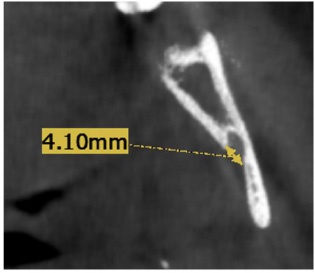

- MF diameter: The axial view was used for measurement (Fig. 3).

Diameter measurement of MF carried out on the axial view.